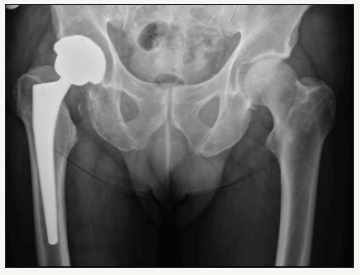

A 64 year old male underwent right total hip arthroplasty for osteoarthritis (Figure 1). A 58mm Pinnacle sector 2 acetabular cup with a neutral Marathon polyethylene liner (28mm ID x 58mm OD) was mated via a 28mm+5 high offset stainless steel Articul/Eze femoral head (12/14 cone) to an uncemented No 14 Corail stem. Post-op recovery was uneventful. Post-op X-Rays showed 37° of inclination of the cup (Figure 2).

figure 2: Post-op right total hip arthroplasty.